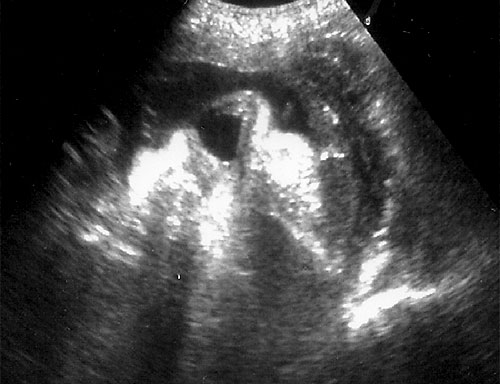

Normal fetal bladder at 18 weeks (left, at arrow). Lovely picture of both uterine arteries around normal bladder (right). This color flow picture documents the presence of the 3 vessel cord with the demonstration of the two uterine arteries coursing around the bladder. - Spine (need two perpendicular views)

Normal cervical spine at 18 weeks (1). Another normal sagittal view of cervical spine seen in third trimester with folds of fat seen (2). Normal thoracic spine at 18 weeks (3). Normal sagittal view of lumbosacral spine at 18 weeks (4). Normal transverse view of lumbosacral spine at 18 weeks (5). - Extremities (hands/feet)